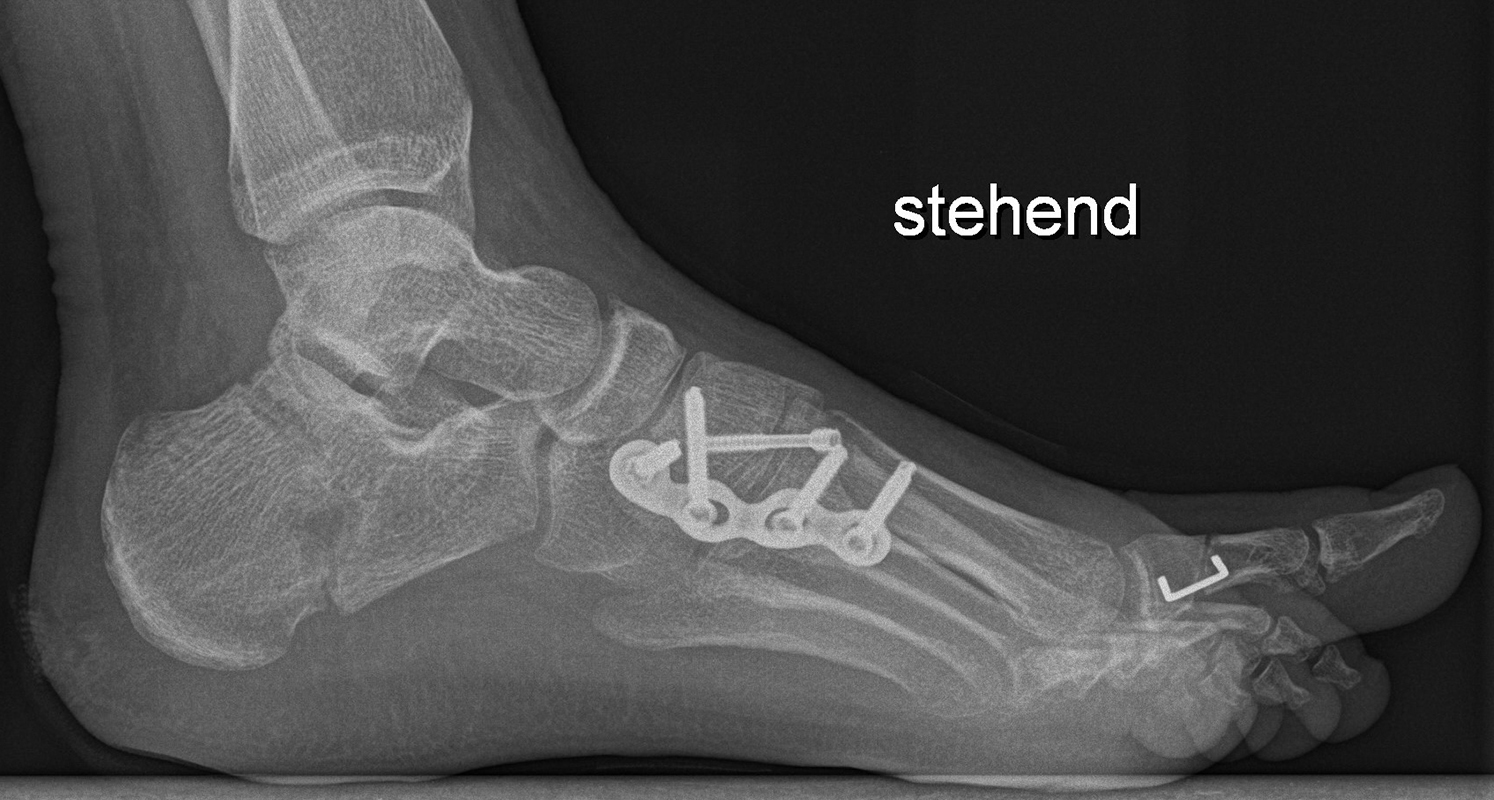

Abb. 40 a-f: Kompletter klinischer und radiologischer Verlauf eines schweren Ballenhohlfußes: Bild im Stand mehrere Ansichten sowie radiologische Diagnostik präoperativ (a), percutane Ablösung der Plantarfaszie als ersten operativen Schritt (b), radiologisch sichtbare Osteot0mien MT I-V sowie klinisches Ergebnis intraoperativ (c-d), klinische Gegenüberstellungen der präoperativen Fehlstellung und der postoperativen Korrektur (e); zweites Beispiel eine spastische Hohlfußfehlstellung im prä- und postoperativen klinischen Verlauf (f).

Zum Lesen der Bildbeschreibung und zur Vollansicht bitte die Bilder anklicken. Bilder: A. Helmers.